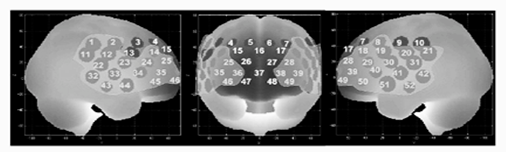

还有两项研究[4、5]采用高通道的fNIRS覆盖左右额叶和枕叶脑区,分别对不同完整性的字母识别以及不同视觉识别速度进行研究,对双侧额叶和枕叶的大脑激活差异进行了分析。(图5)

图5 头部通道放置示意图